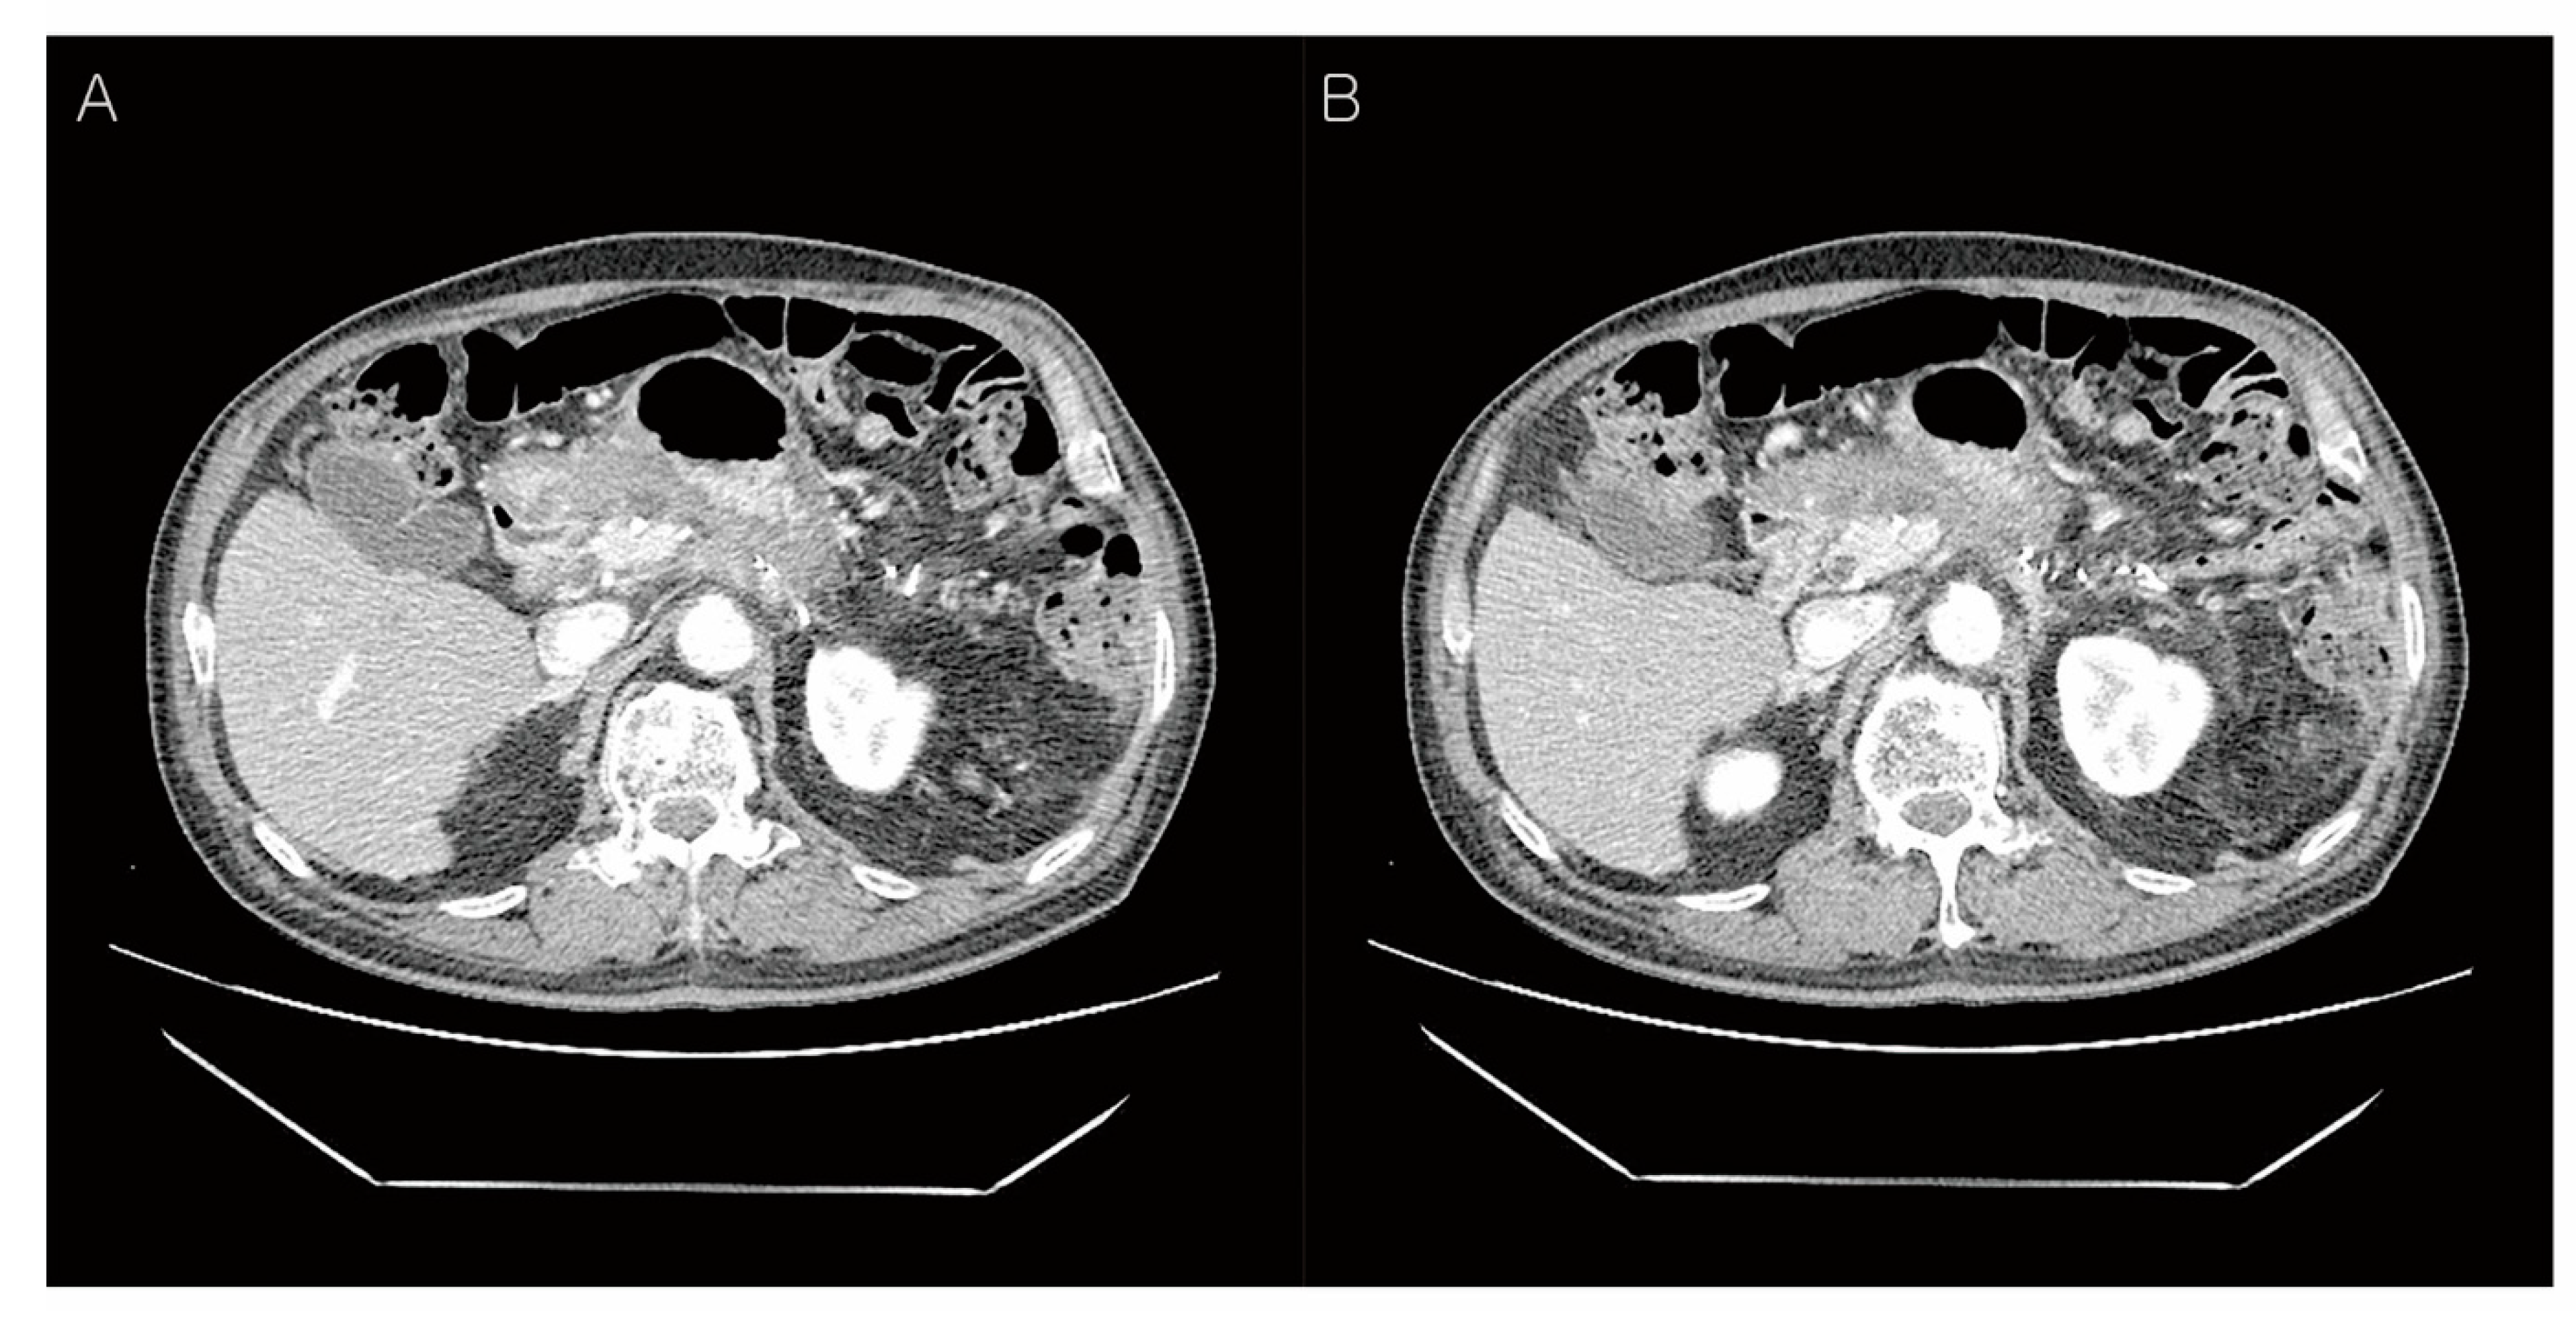

Abdominal CT findings post-operation, two months later. The patient underwent postoperative radiotherapy for three weeks. After two months, abdominal CT findings showed more prominent soft tissue thickening adjacent to the common hepatic artery (A) and 3.8 cm loculated fluid collection at the resection margin of the pancreas (B). This CT finding showed local recurrence at the resection margin of the pancreas, therefore, adjuvant FOLFIRINOX chemotherapy was Carried out 12 times for nine months.